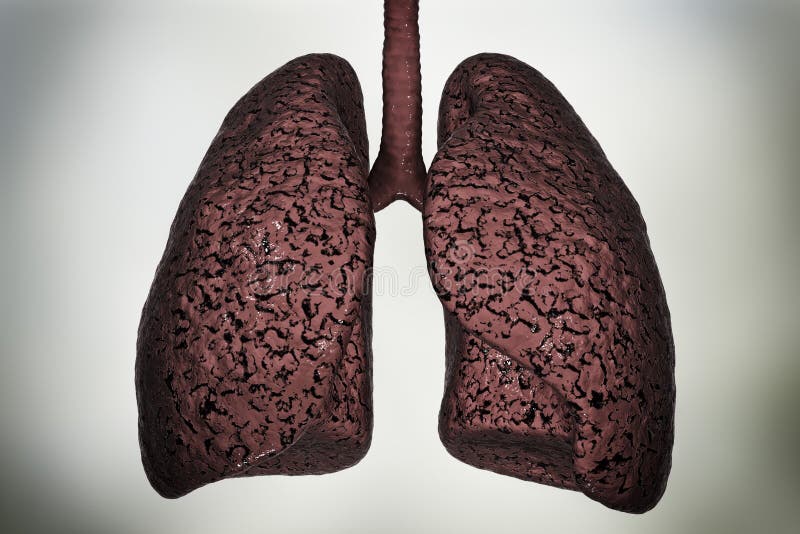

Здоровый образ жизни: Влияние курения

Раздел: Моменты озарения